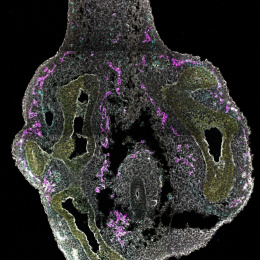

Confocal Micrograph

Lymphatic vessels (green) carry white-blood-cell-containing fluid called lymph throughout the body. In cancer, they can also serve as pipelines for the metastatic spread of tumors. This image is part of an investigation that uses new tools to search for the genes that drive lymphatic growth and development.